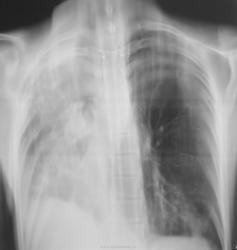

По рентгенограммам фиброторакс как бы неполный, однако, на представленных томограммах правый главный бронх в виде культи, но нечётко видимой. И металл. зажимы в срезы не попали. Там точно всё удалено?

Левое лёгкое с патологией и в нижней доле и в верхней.

Неоднозначно всё

Согласно документам - пульмонэктомия.

Ну пульмонэктомия-значит пульмон эктомия , ничего нового.Только надо иметь ввиду грубое смещение органов средостения и медиастинальная грыжа.

С медиастинальными грыжами понятно. А что ещё светится на месте удалённого лёгкого? При фибротораксе такого не может быть. Когда была операция? И клиники хоть ложку надо.